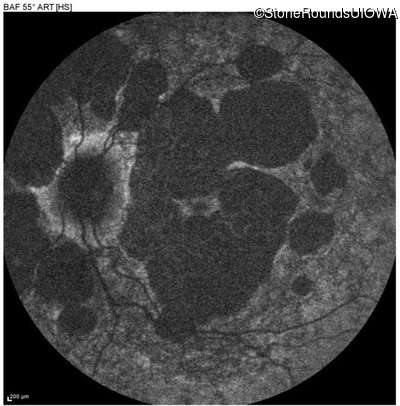

Age at visit: 51 years

This 51 year old woman first experienced some abnormality in her distance vision when she was 27 years old. She feels that her vision has been stable since that time.

Diagnosis & molecular findings

AR Stargardt Disease ABCA4 Gly1507Arg GGG>AGG IVS42+1 G>A AR